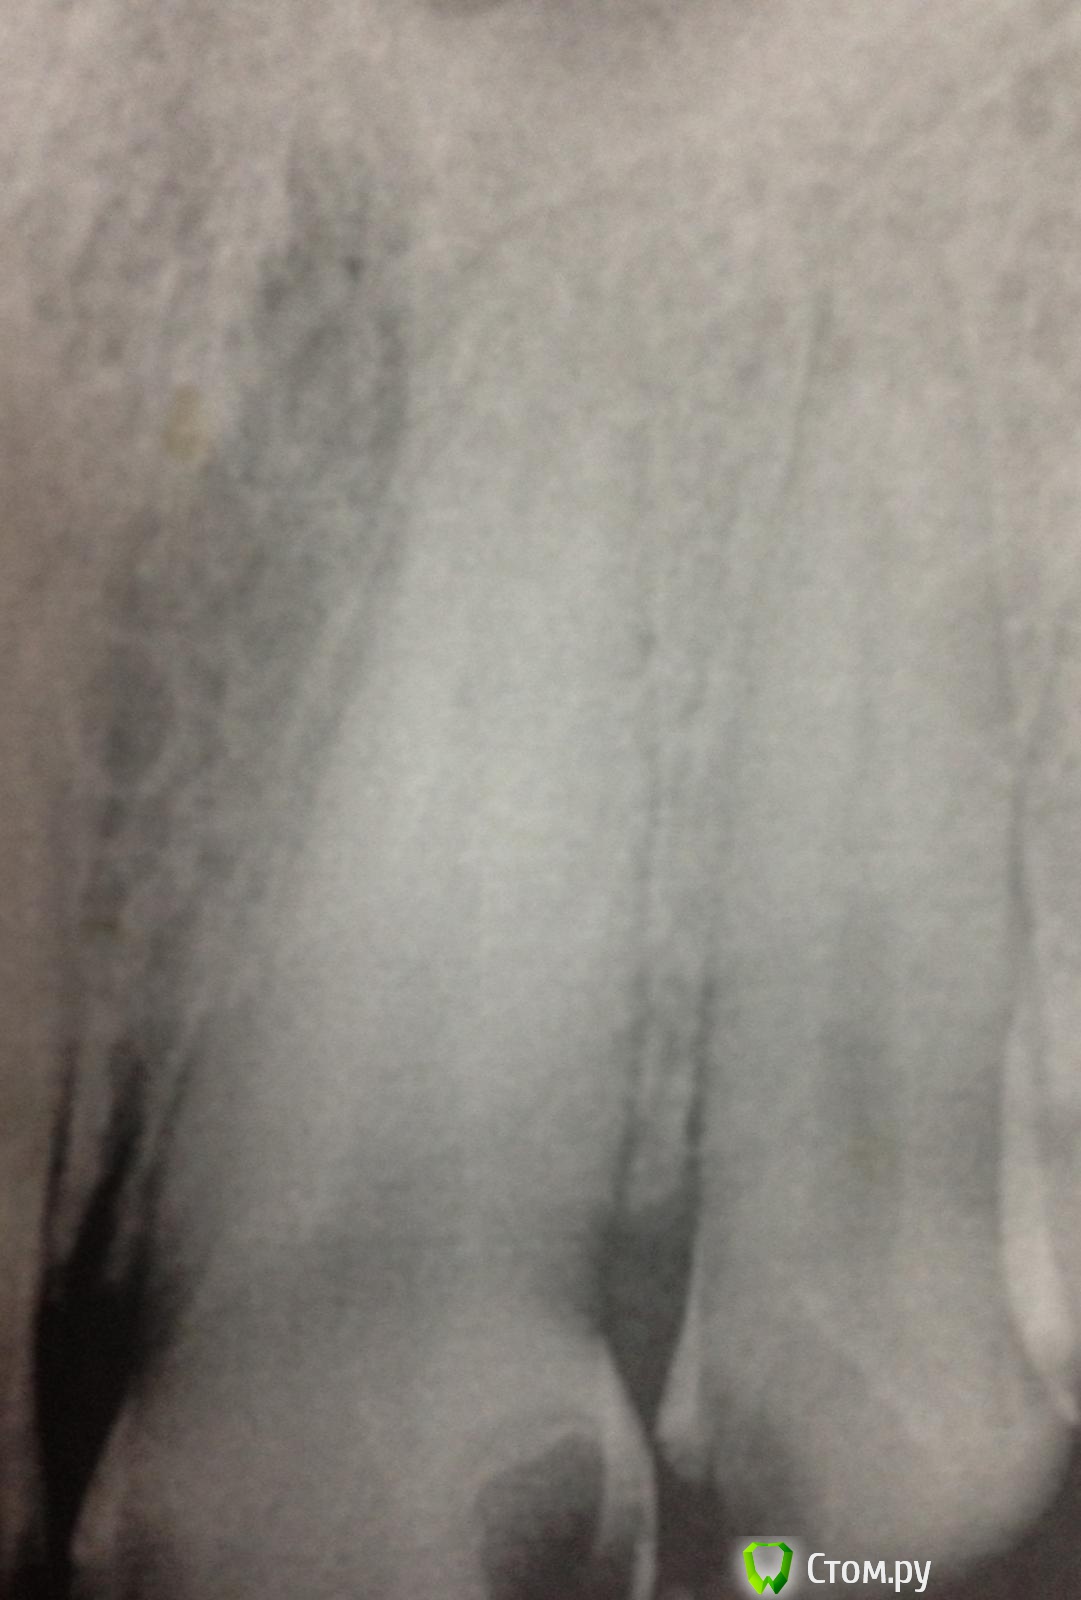

SSTi Опубликовано 7 октября, 2014 Автор Поделиться Опубликовано 7 октября, 2014 Как я не люблю широкие каналы! Понял это сегодня. 11. Сломан зуб давно. Болел. Потом не болет и тд. Стандартно. Весь в зарослях из десны. Сделали снимок. Ну, думаю, широкий и широкий. Ну и круто.Убрал десну. Феррул есть. Одел коффер. Преп. Вскрыли полость - там труп пульпы выглядывает и машет. Убрал эту красоту. Помылся. Померился. Машинными файлами посреб стенки, но толку мало. Начал делать уступ - 50 маленький. 55 мал. 60 мал, 70 мал. 80 - и тут я хоть уперся чуточку. Сделал упор как смог. Еще вымылся (мылись час в общей сложности). Латералка. Вот лучше бы семерку полечил, чем такую единицу. 1 Ссылка на комментарий

SSTi Опубликовано 7 октября, 2014 Автор Поделиться Опубликовано 7 октября, 2014 П.с. Был в шоке от гутты. 80 номер торчал из линейки калибровойной на 3.5 мм примерно. Как так то??? Ссылка на комментарий